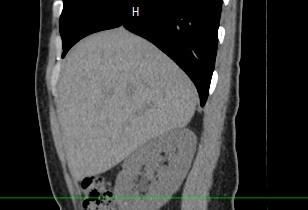

Печеночная ткань имеет обильное кровоснабжение, поэтому часто ультразвуковая диагностика заболеваний печени затруднена. Одним из наиболее информативных методов диагностики является мультиспиральная КТ печени, которая может проводиться в стандартном режиме и с внутривенным болюсным контрастированием. Введение йодсодержащего контрастного вещества значительно повышает диагностическую ценность компьютерной томографии и позволяет, в частности, выявить злокачественное образование на ранней стадии, отличить доброкачественный процесс от злокачественного, визуализировать изменения внутрипеченочных желчных протоков и многие другие патологические процессы.

В нашей клинике сканирование печени выполняется на современном 128-срезовом томографе экспертного класса TOSHIBA AQUILION CXL, который производит послойное сканирование исследуемого органа с последующей цифровой обработкой полученных данных для создания трехмерных изображений печени высокого качества и контрастности. Увеличенное количество детекторов, вмонтированных в аппарат, обеспечивает быстрое время исследования и пониженные дозы рентгеновского излучения, получаемого пациентом.

- увеличение органа в размерах;